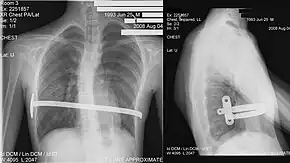

-

Cross sectional scan of a chest with pectus excavatum -

Pectus excavatum on PA chest radiograph with shift of heart shadow to the left and radioopacity of the right paracardiac lung field

Many scales have been developed to determine the degree of deformity in the chest wall. Most of these are variants on the distance between the sternum and the spine. One such index is the Backer ratio which grades severity of deformity based on the ratio between the diameter of the vertebral body nearest to xiphosternal junction and the distance between the xiphosternal junction and the nearest vertebral body.[19] More recently the Haller index has been used based on CT scan measurements. An index over 3.25 is often defined as severe.[20] The Haller index is the ratio between the horizontal distance of the inside of the ribcage and the shortest distance between the vertebrae and sternum.[21]

Chest x-rays are also useful in the diagnosis. The chest x-ray in pectus excavatum can show an opacity in the right lung area that can be mistaken for an infiltrate (such as that seen with pneumonia).[22] Some studies also suggest that the Haller index can be calculated based on chest x-ray as opposed to CT scanning in individuals who have no limitation in their function.[23]